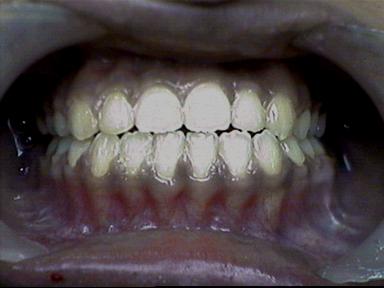

After Treatment Intra Oral